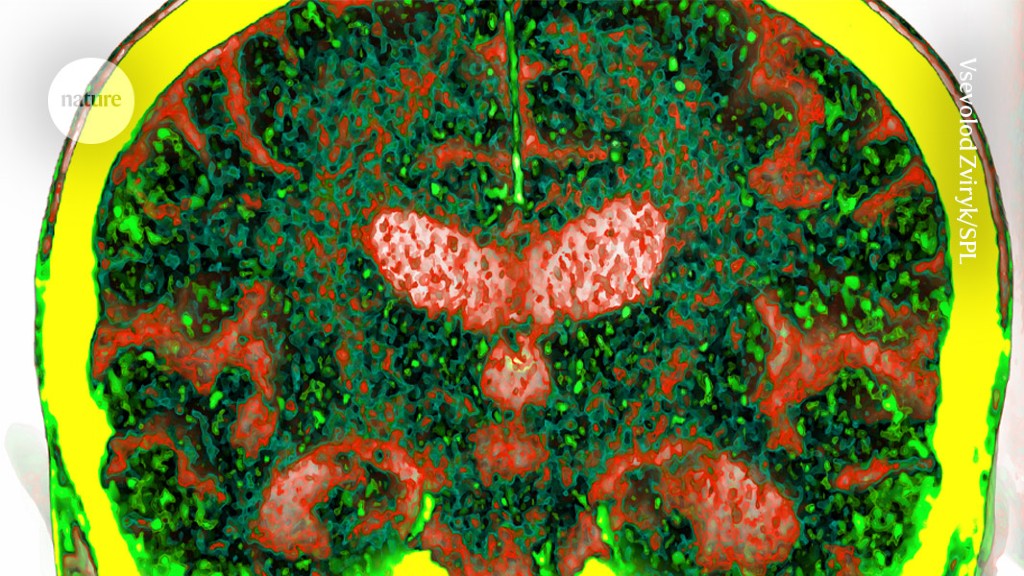

Featured image for "Blood Protein Test Predicts Dementia 15 Years in Advance"

A study analyzing blood proteins has identified biomarkers that can predict the risk of developing dementia up to 15 years before diagnosis, potentially leading to the development of blood tests for early detection of diseases such as Alzheimer's. High levels of four proteins - GFAP, NEFL, GDF15, and LTBP2 - were found to be strongly associated with dementia, and a predictive model combining these biomarkers with demographic factors showed about 90% accuracy in predicting the incidence of dementia subtypes more than ten years before diagnosis. While the findings are promising, further validation is needed before these biomarkers can be used as clinical screening tools.